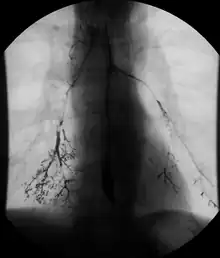

Normal barium swallow fluoroscopic image, showing the ingested barium sulfate being induced down the oesophagus by peristalsis. | |

An upper gastrointestinal series, also called a barium swallow, barium study, or barium meal, is a series of radiographs used to examine the gastrointestinal tract for abnormalities. A contrast medium, usually a radiocontrast agent such as barium sulfate mixed with water, is ingested or instilled into the gastrointestinal tract, and X-rays are used to create radiographs of the regions of interest. The barium enhances the visibility of the relevant parts of the gastrointestinal tract by coating the inside wall of the tract and appearing white on the film. This in combination with other plain radiographs allows for the imaging of parts of the upper gastrointestinal tract such as the pharynx, larynx, esophagus, stomach, and small intestine such that the inside wall lining, size, shape, contour, and patency are visible to the examiner. With fluoroscopy, it is also possible to visualize the functional movement of examined organs such as swallowing, peristalsis, or sphincter closure. Depending on the organs to be examined, barium radiographs can be classified into "barium swallow", "barium meal", "barium follow-through", and "enteroclysis" ("small bowel enema"). To further enhance the quality of images, air or gas is sometimes introduced into the gastrointestinal tract in addition to barium, and this procedure is called double-contrast imaging. In this case the gas is referred to as the negative contrast medium. Traditionally the images produced with barium contrast are made with plain-film radiography, but computed tomography is also used in combination with barium contrast, in which case the procedure is called "CT enterography".[1]